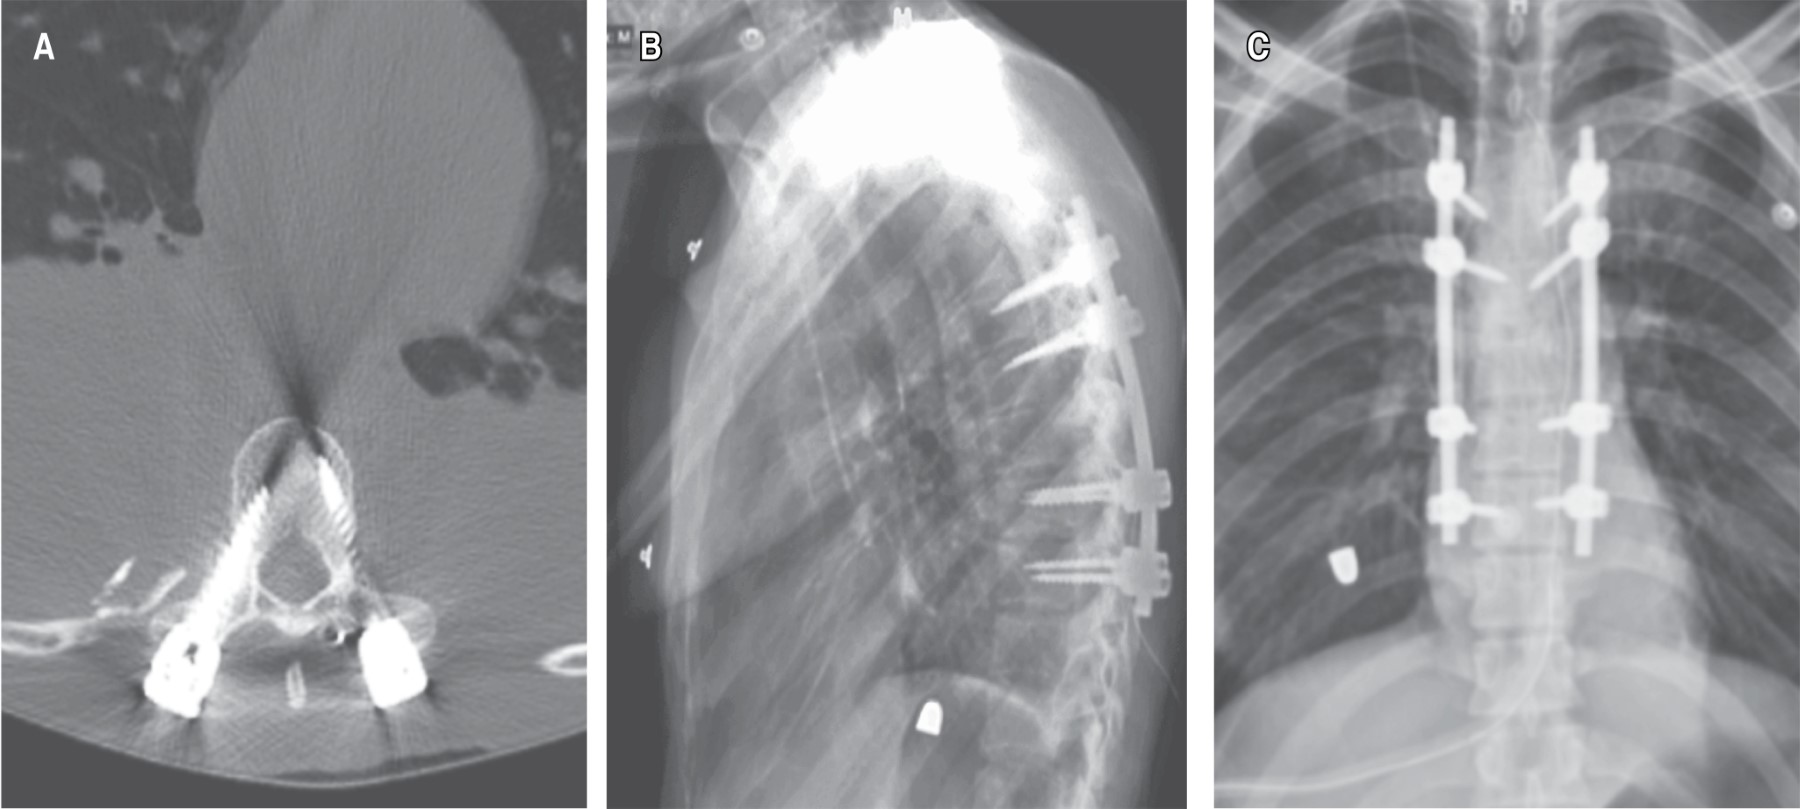

Se interconsulta al servicio de cirugía de columna, quien concluye en los siguientes diagnósticos a partir de exploración y hallazgos tomográficos (Figuras 1 y 2): fractura por estallido de T5 y T6 Gustillo-Anderson IIIA, fractura de los pedículos derechos de T6 y T7, traumatismo raquimedular secundario a proyectil por arma de fuego Frankel A, ASIA A y fractura de articulación costovertebrales de arcos costales 8 y 9; por lo que a los 11 días de estancia intrahospitalaria se procedió a instrumentación torácica posterior con hemilaminectomía para descompresión, estabilización y movilización, con pronóstico malo para la función. Durante la intervención se observa lesión del pedículo y lámina T5, por lo que no es posible instrumentar dicho nivel, optando por instrumentar dos niveles por encima y dos niveles por debajo. Se realizó colocación de tornillos transpediculares poliaxiales en T3, T4, T6 y T7 con colocación de 30 cc de injerto óseo en chips (Figura 3), asistido por fluoroscopia.